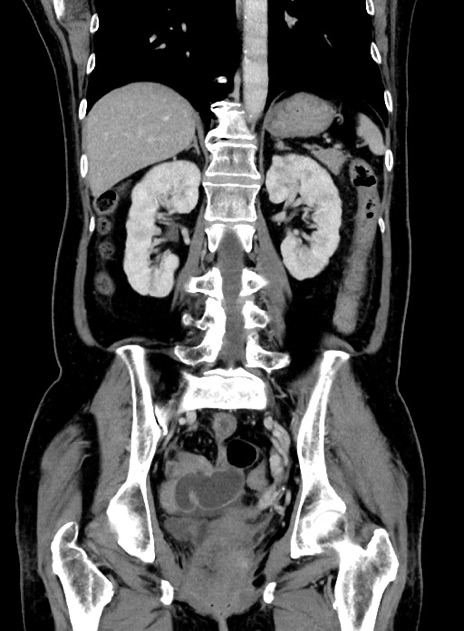

症例9(冠状断像)

【症例】 60歳代女性

【主訴】むかつき、みぞおちの痛み

【現病歴】3日前よりむかつきがあり、食事がとれない。

【既往歴】糖尿病

【身体所見】発熱なし、心窩部圧痛軽度あるも、腹膜刺激症状なし。

【データ】WBC 7400、CRP 1.92